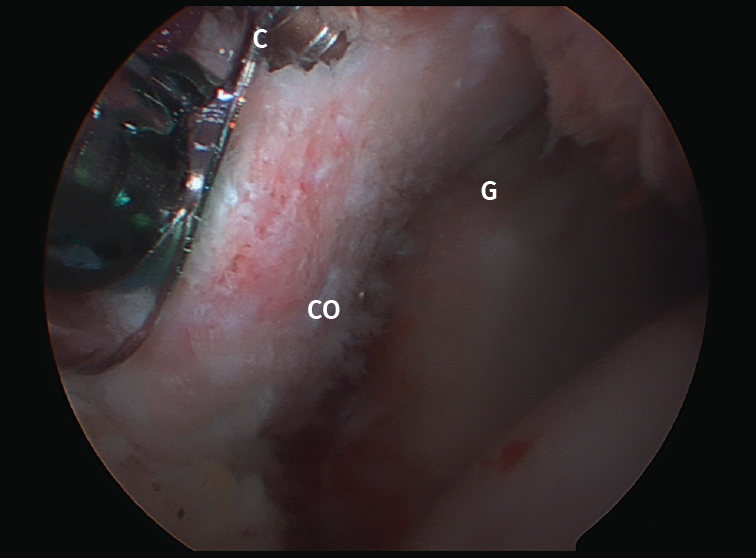

Figure 5. Latarjet procedure, arthroscopic technique. View of arthroscopic coracoid (CO) fixation from the J portal. C: guide cannula for placing the screws; G: anteroinferior part of the glenoid cavity.

Satisfactory outcomes and great effectiveness have been reported with this procedure in soccer players(65) and rugby players(66). Good outcomes have also been described in successfully restoring shoulder stability in elderly patients(67) and when used in revision surgery(68). More recently, the results obtained with the arthroscopic Latarjet procedure (Figure 5) have been reported, with outcomes equivalent to those of the open procedure, though the laparoscopic approach is clearly more demanding from the technical perspective(57,69).